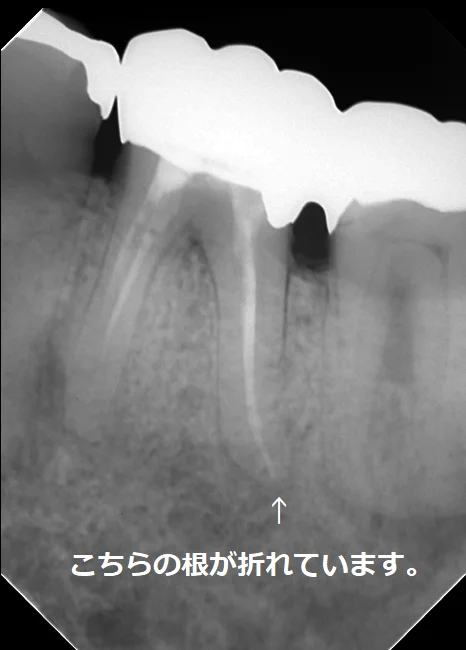

歯の抜歯の原因の一つである歯根破折についてです。

歯根破折というのは、力に耐えられず歯の根が折れてしまうことです。(こちらの記事でも書きましたね。)

神経の治療を行う事で、健康な歯の部分が減ってしまい、力に耐えきれなくなってしまう事があります。

また、一昔前までは・・・

こーんな感じで

「神経の治療後はメタルコア(金属の土台)を入れる」

というのが歯科界での常識でした。

当然金属は歯よりも固いので、噛む度に楔のような作用が働き、歯が折れる主たる原因となってしまっていました。

現在では歯根破折のリスクを減らすことが出来るファイバーコアが保険適用内でも認められていますので、わざわざ歯根破折のリスクが圧倒的に高いメタルコアを入れる機会は無くなってきましたが・・・

その一昔前に入れられたメタルコアが患者さんのお口の中にはまだまだ残っています。

また一度削った歯は当然二度と元には戻せませんので、一度メタルコアを入れられた方についてはメタルコアを除去した後も歯根破折のリスクは高い状態が維持されてしまいます。

こちらの方は私が治療に入った時にはファイバーコアが入っていましたが・・・

その前は太いメタルコアが入れられていたそうです。

実際に被せ物を除去して根の状態を直接肉眼で確認したところ、後ろ側の根がレントゲンには写らないラインで真っ二つに折れていました。

通常、歯根破折が起こった歯の第一選択は「抜歯」になります。

折れてしまうと元に戻すことが出来ませんからね。

(一部歯根破折の接着修復というテクニックもありますが・・・あまり予後が良いとは思えず私は行っていません。)

今回の場合も2本の根の管があるように最初のレントゲン上では写っていましたが、実際にはその2本は非常に細い道でつながっており、しかも元々の根の管がその細い道の中に隠れていました。

最初のレントゲンに比べると神経の治療後の薬が根の先まで綺麗に入っているのが分かるかと思います。